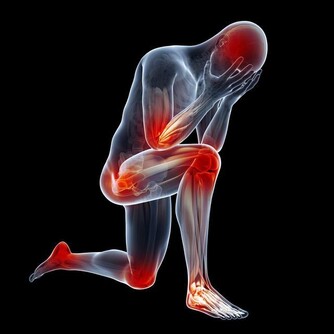

我們的血液不是固定在某一部位,而是在不停流通的,在蹲著的時候,腿部擠壓在一塊,腿部的血管會受到壓迫,它一受到壓迫,血液就無法很好的流通到腿部,這時候腿部是處於缺血的狀態的。蹲久了腿麻就是因為腿部缺血造成的。

等到你站起身後,腿部的血管壓迫消失了,這個時候身體的血液會集中湧向到腿部,改善腿部缺血的情況。血液集中湧向到腿部後,腿部缺血的情況會得到改善,不過上身尤其是大腦的血液就會變少,這時候大腦會出現缺血的情況。而大腦一缺血就會出現頭暈眼花站不穩的情況。等過幾十秒或幾分鐘,血液循環會恢復到常態,這時候頭暈眼花的情況消失。

這種現象的發生,是正常的生理現象,被稱之體位性低血壓,不是低血糖也不是貧血造成的。